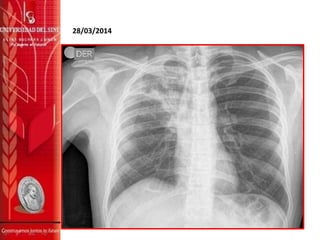

28/03/2014

ANALISIS MEDICINA INTERNA

Paciente masculino de 46 años de edad, con cuadro clínico de +/- 6

meses de evolución de tos seca productiva, esputo de color verdoso

sin hemoptisis, niega disnea, asociado a perdida de peso, tratado de

manera ambulatoria sin mejoría, mostrando agudización de la

sintomatología desde hace 3 días acompañado de fiebre no

cuantificada, escalofríos y sudoración nocturna, motivo por el cual

consulta al servicio de atención prioritaria de su EPS de donde

remiten para valoración por medicina interna, encontrando además

de lo referido y hallado al examen físico, imagen radiológica

sugestiva de cavitación a nivel apical pulmonar derecho que aunado a

antecedente personal de TBC hace mas de 20 años con tratamiento

incompleto, se decide hospitalizar en iniciar estudios

complementarios en aras de descartar o confirmar TBC pulmonar así

mismo se decide iniciar antibioticoterapia biconjugada ante posible

sobreinfección bacteriana y por alteración estructural pulmonar se

decide iniciar claritromicina y piperazilina tazobactam. Trae reporte

de BK de esputo tomados hace 3 meses, negativos en ese momento.